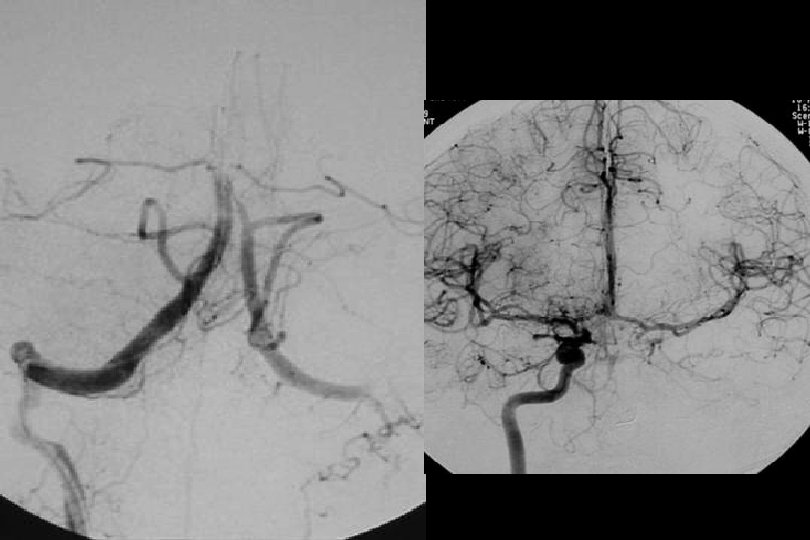

71 y kadın hasta En iyi medikal tedavi altında post fossa iskemik ataklara neden olan baziler stenoz

Sağ brakial yaklaşım ile Reflex /Navien servikal R- VA’e ve intrakraniyal segmente ilerletilmiştir.